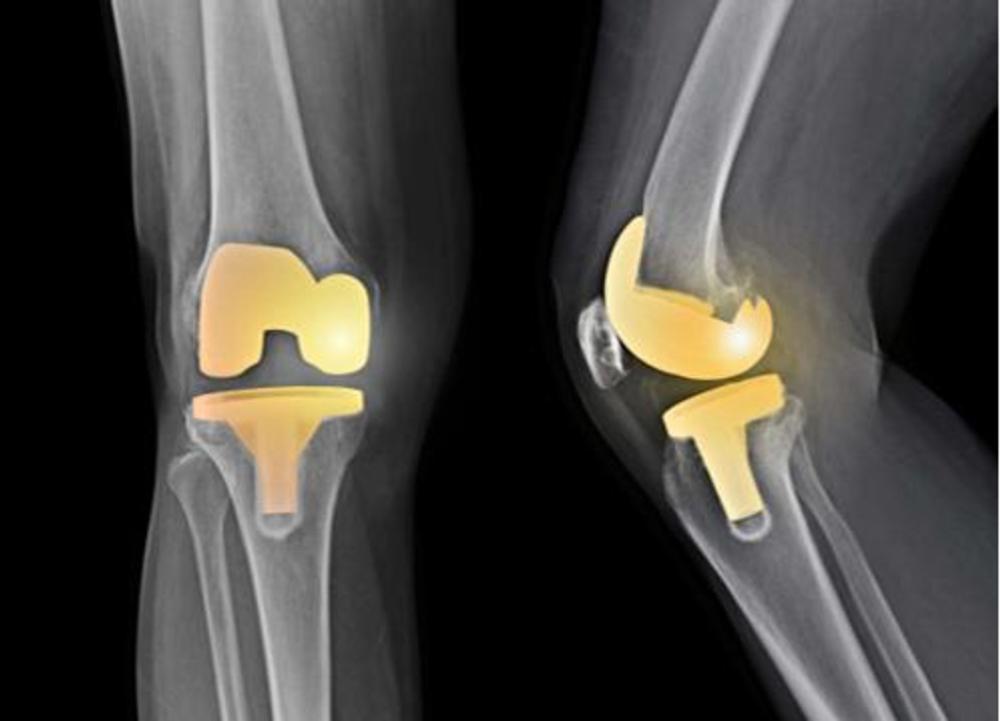

Figure 6. Image shows knee arthroplasty (replacement).

High-res (TIF) version